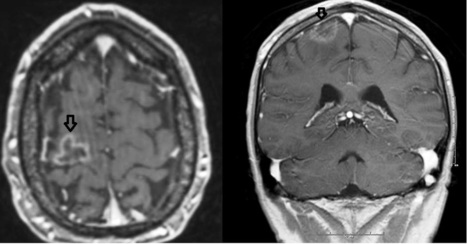

Brain Metastases from Colorectal Cancer: Microenvironment and Molecular Mechanisms Epidermal Growth Factor Receptor Signaling Amplification and overdose of epidermal growth factor receptor (EGFR) were identified in several ... Read Document

Systematic review EGFR tyrosine kinase inhibitors versus cranial radiation therapy for EGFR mutant non-small cell lung cancer with brain metastases: A systematic ... Access Content

422 Expert Rev. Anticancer Ther. 12(4), (2012) Editorial The EGFR tyrosine kinase inhibitors (TKIs), gefitinib and erlotinib, considered active agents, have became part of the ... Return Document

Treatment of Brain Metastasis from Lung Cancer Alexander Chi 1 and Ritsuko Komaki 2,* 1 Department of Radiation Oncology, for patients with EGFR mutation and brain metastases from lung adenocarcinoma, WBRT delivered concurrently with EGFR inhibitors produced a response rate of 84% [175]. ... Fetch Here

Mini-review Epidermal growth factor receptor tyrosine kinase inhibitors in the treatment of central nerve system metastases from non-small cell lung ... Read Content